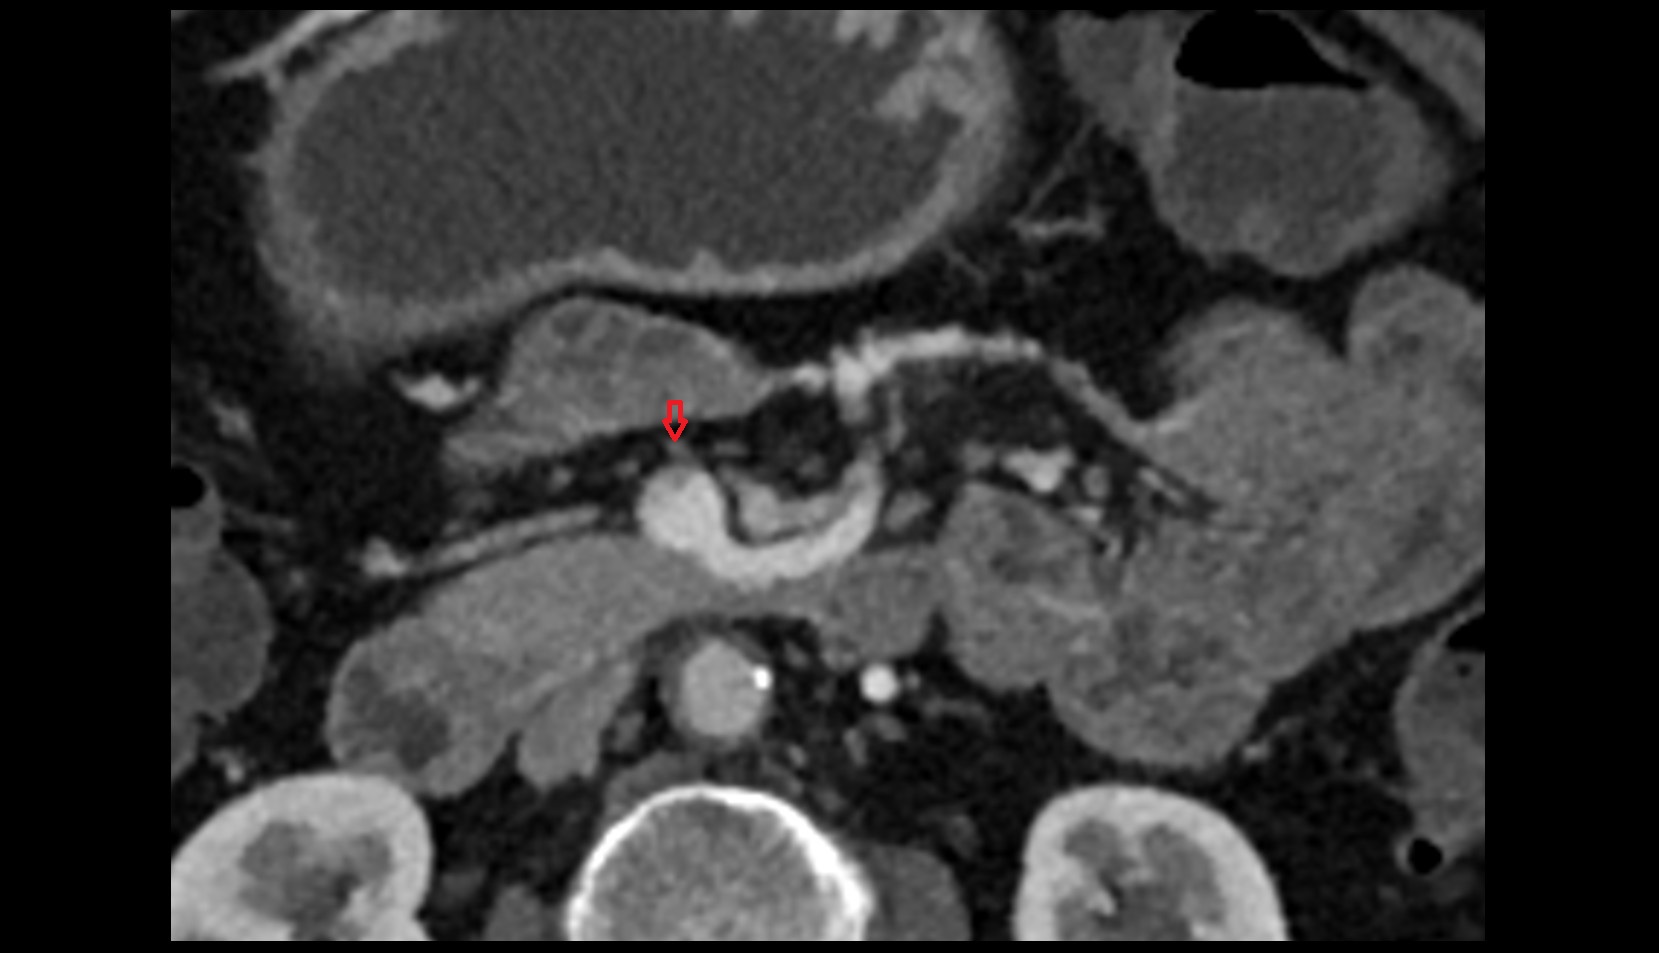

- Pancreatic duct

- Neck of pancreas

- Head of pancreas

- Uncinate process of pancreas

- Body of pancreas

- Tail of pancreas

- Common bile duct

- Common hepatic duct

- Left hepatic duct

- Right hepatic duct

- Cystic duct